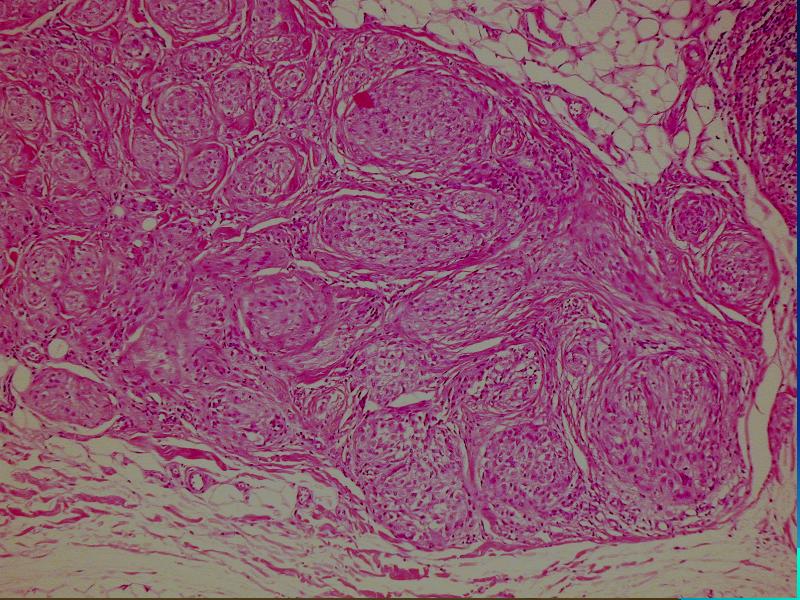

Opis pierwotny: w skórze właściwej /środkowa i dolna część/ obecny ziarniniak zbudowany ze zrazików zawierających komórki z obfitą cytoplazmą z pęcherzykowatymi jądrami z wyraźną błoną jądrową. Pojedyncze wielojądrowe komórki. Wokół zrazików i wewnątrz nich obecne limfocyty. Zmiana obecna również w tkance podskórnej. Usunięcie nieradykalne.

W badaniu mikroskopowym typowych przypadków (40%) stwierdza się dwa komponenty: fibroblastyczny i histiocytarny z obecnością komórek olbrzymich wielojądrowych.

Komórki histiocytarne tworzą drobne guzki otoczone wiązkami komórek fibroblastycznych. Komórki wielojądrowe rozrzucone są nieregularnie wśród wyżej wspomnianych struktur. Mitozy nieliczne. Niekiedy ogniskowa atopia. Miejscami wylewy krwawe i złogi hemosyderyny i skupiska limfocytów.

Fibroblasty tworzą krótkie wiązki oplatając guzki, tworząc splotowaty układ, który może upodabniać zmianę do fibromatozy.